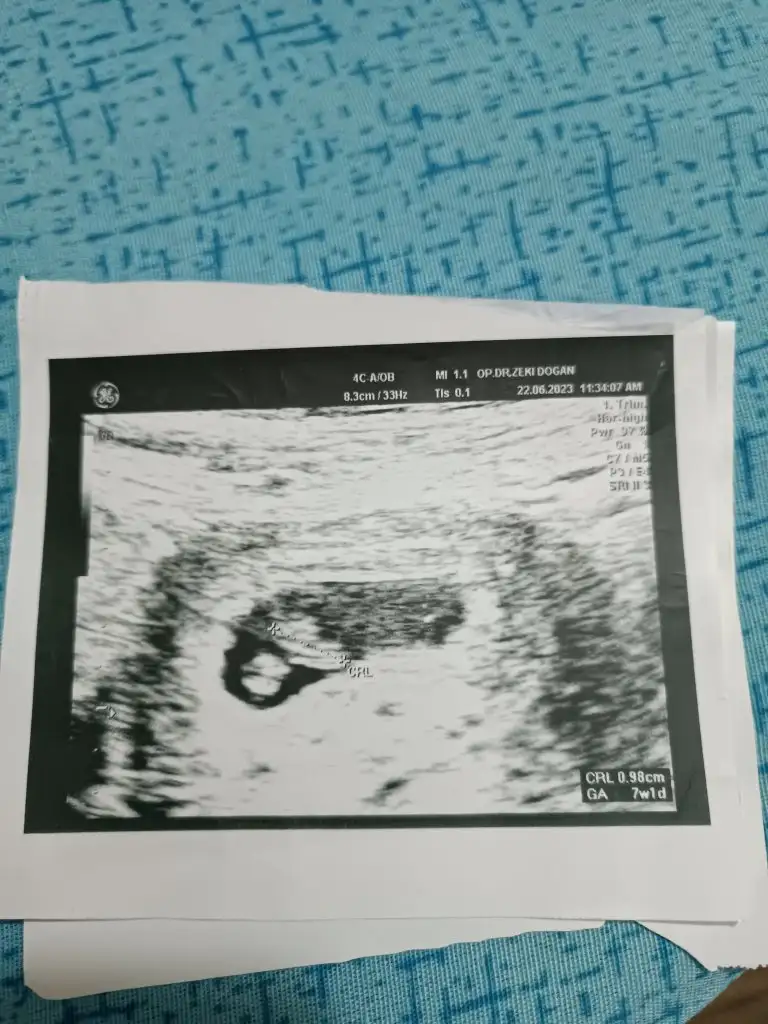

Merhaba banada yorum yaparmsnz. Karindan 8 haftalik.Çok sevindim.

Bu da şirin bir kızMerhaba banada yorum yaparmsnz. Karindan 8 haftalik.

Biri 8 haftalık iken diğeri ise 14 haftadaBaşka bir ultrason varsa önceki haftalara dair daha net görünen

Kıza benziyor canımBiri 8 haftalık iken diğeri ise 14 haftada